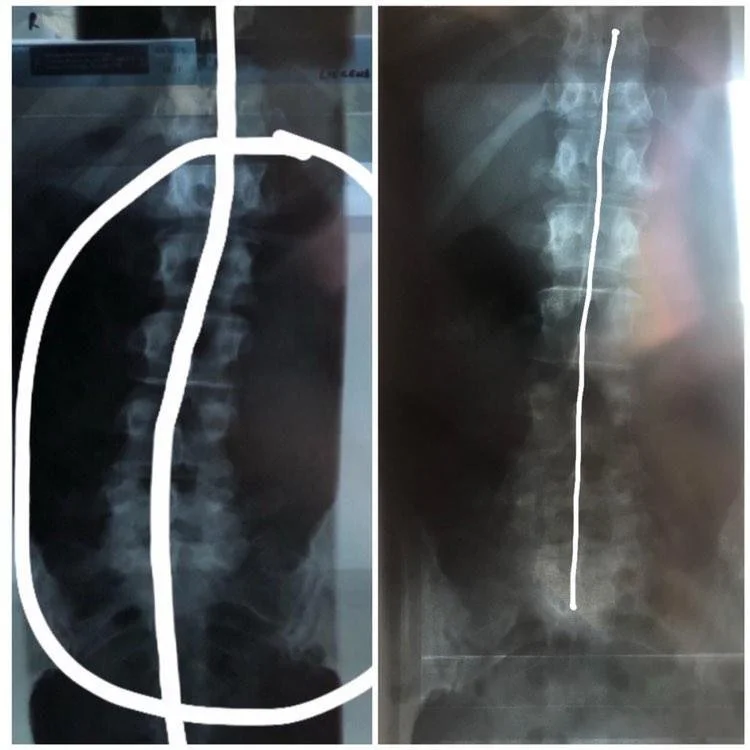

Xrays cross-comparison

Xray comparison of the same patient before and after the therapy clearly, objectively optically showcases the results documented by medical professionals, and ascertains the usefulness and effectiveness of Nathan Jelicic s non-invasive form of therapy, proving it has tangible,valuable real-world practical application.

Initial checkup was performed by a medical doctor dated 09.December.2019. Based on Xray findings , medical diagnostic paperwork was issued to the patient. (left original, right translation)

X-ray thoracic spine / lumbar spine in 2 planes from 09.12.2019.

After utilizing Nathan Jelicic s non-manual, non-invasive therapy, new xrays were made and accompanying medical paperwork was issued to the patient based on those findings, dated 27.January.2020. (slightly over 1 month apart from the initial checkup)

X-ray lumbar spine in 2 planes with thoraco-lumbar transition from 27.01.2020.

Positioning of the lumbar spine and lower thoracic spine with regular alignment of the recorded vertebral bodies without height reduction or wedging. A significant scoliosis is not present. No significant narrowing of the intervertebral disc compartments.

• No evidence of spondylolisthesis, no significant scoliosis.